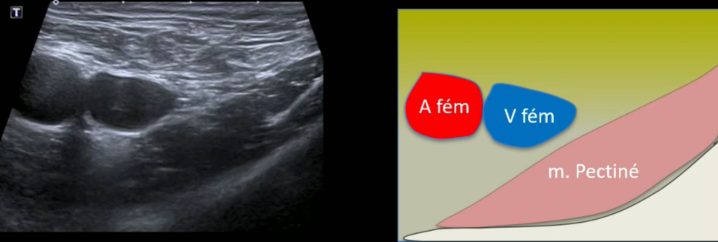

Hernie fémorale

Technique

- Permet de tester le valsalva

- Repères anatomique

- Vx fémoraux

- Muscle pectiné

crural crurale femoral